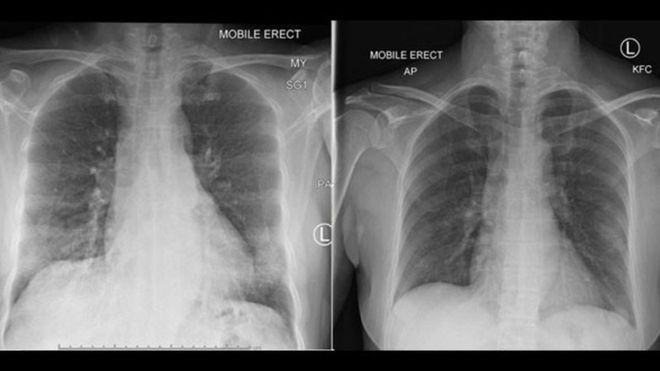

Keempat tipe sel imun ini diamati dengan melacak seorang pasien yang mengalami kasus virus corona dengan gejala ringan-sedang dan tidak punya masalah kesehatan sebelumnya.

Pasien perempuan berusia 47 tahun dari Wuhan, China itu, telah mendatangi sebuah rumah sakit di Australia. Dia pulih dalam 14 hari.

Tiga hari sebelum kondisi perempuan ini mulai membaik, sel-sel tertentu dapat dilacak pada aliran darahnya. “Pada pasien dengan influenza, sel-sel yang sama ini juga muncul pada waktu yang hampir sama sebelum si pasien kemudian membaik,” kata Prof Kedzierska.